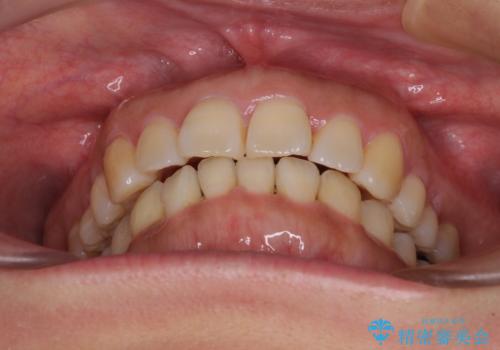

- 上下前歯の叢生を気にして来院された患者様です。

費用を抑え、期間もあまりかけずに治療をしたいとのことで、インビザライン・ライトを用いて矯正治療を行うこととしました。